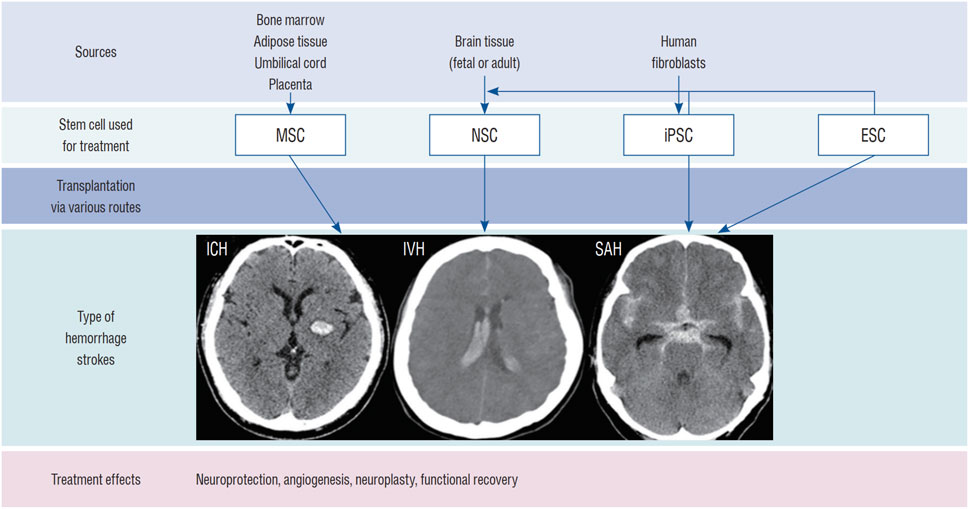

综述结果表明,神经干细胞治疗ICH的机制涵盖替代神经元、免疫调节与促进血管生成等多重途径;其来源可分为内源性激活与外源性移植,后者包括原代培养、多能干细胞分化及体细胞重编程;输送途径主要有立体定向脑内注射、经脑脊液移植及血管内注射,各有优劣。

其次,多能干细胞分化是另一重要外源性途径,主要包括胚胎干细胞和诱导多能干细胞。胚胎干细胞虽能分化为神经干细胞,但存在伦理争议、免疫排斥和致瘤风险;而诱导多能干细胞通过体细胞重编程获得,避免了伦理问题,但制备过程耗时且存在类似的安全隐患,制约了其临床转化。

最后,体细胞重编程和转分化技术提供了更直接的生成方式,例如利用病毒载体或转录因子将成纤维细胞等体细胞转化为神经干细胞或神经元。尽管转分化方法相对简便,但病毒载体可能带来致瘤风险,且转化过程可能产生不必要的副产物,仍需进一步优化以提高安全性与效率。

目前,神经干细胞移植主要通过脑内移植、鞘内/脑室内注射(经脑脊液途径)、血管内注射和鼻内给药等途径进行。最常用的方法是直接脑内移植。然而,每种方法都有其独特的优缺点,目前尚未确定统一的移植途径(图1)。

总体而言,胚胎干细胞和诱导多能干细胞虽分化潜能强,但分别面临伦理、免疫原性和致瘤性挑战;神经干细胞修复功能明确但获取困难;间充质干细胞则因易得性和良好的安全性被广泛研究。